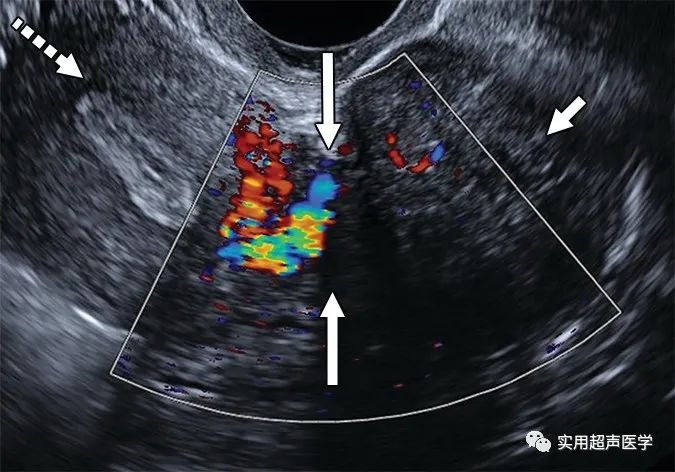

36 岁女性,彩色多普勒超声图像显示子宫(虚线箭头)和实心病变(短实心箭头)之间的桥接血管(长实心箭头),证实外生性浆膜下平滑肌瘤,而不是卵巢病变。由于最常见的附件实性肿块是外生性肌瘤,因此当未看到单独的卵巢且怀疑卵巢病因时,谨慎的做法是寻找与子宫的联系。